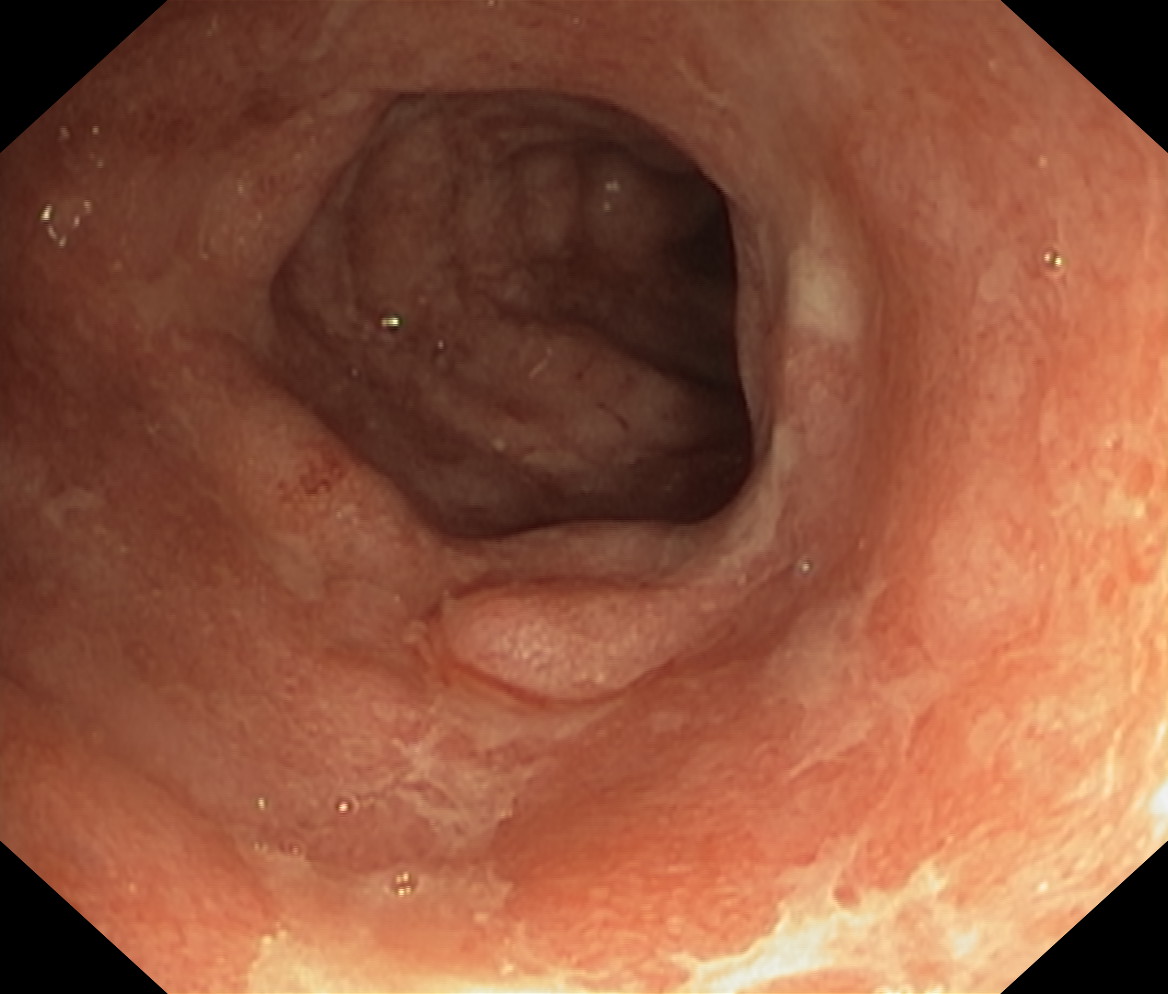

Zapalenie wrzodziejące...

Zapalenie wrzodziejące jelita grubego